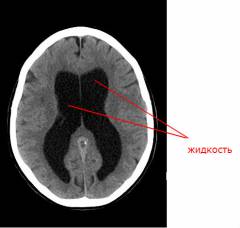

Нейросонография – ультразвуковое исследование черепа. Кости черепа плохо пропускают ультразвук, поэтому исследование можно проводить только у детей младшего возраста, у которых не зарос большой родничок. Исследование позволяет осмотреть внутричерепные структуры и выявить гидроцефалию.

-

Компьютерная томография (КТ) и магнитно-резонансная томография (МРТ). Это более точные исследования. При помощи компьютерной томографии можно не только выявить гидроцефалию, но и установить её причину. Современные аппараты для МРТ позволяют оценить движение спинномозговой жидкости. Для того чтобы получить точные результаты, необходимо, чтобы во время исследования ребенок был неподвижен. Детям младшего возраста часто приходится давать легкий наркоз.